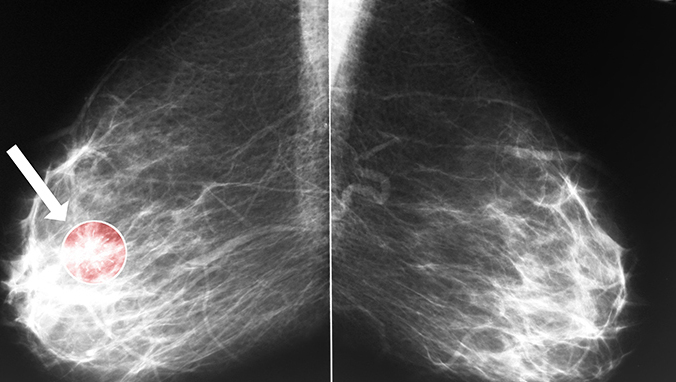

晚期肺癌肝转移患者表现为消瘦、肝区疼、黄疸等,血体检可发现肝大,质中或硬,边缘不规则,表面不平等肝转移特征,CEA可持续升高。清检查除谷丙及谷草转氨酶、碱性磷酸酶明显升高外,乳酸脱氢酶及r一谷氨酷基转换酶均可明显增高。早期弥漫性肺癌肝转移可无自觉症状,查体无异常发现,有时ALT或AST(谷丙或谷草转氨酶)轻中度升高,B超可有弥漫性不均质改变,应注意与其他肝脏疾病鉴别。